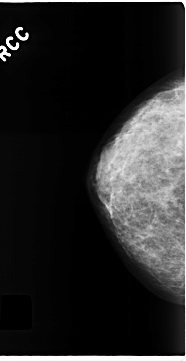

C_0199_1.RIGHT_CC

RIGHT_CC LINES 4688 PIXELS_PER_LINE 2416 BITS_PER_PIXEL 12 RESOLUTION 50 NON_OVERLAY